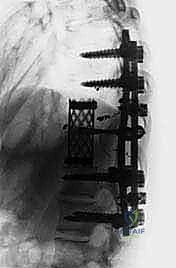

المرحلة الثانية: تثبيت المسامير وبناء الدعامة المؤقتة

قبل البدء في إزالة الفقرة المصابة، يجب تأمين استقرار العمود الفقري. يتم إدخال مسامير التيتانيوم (Pedicle Screws) في الفقرات السليمة فوق وتحت الورم، وتوصيلها بقضبان معدنية مؤقتة لضمان عدم انهيار العمود الفقري أثناء الاستئصال.